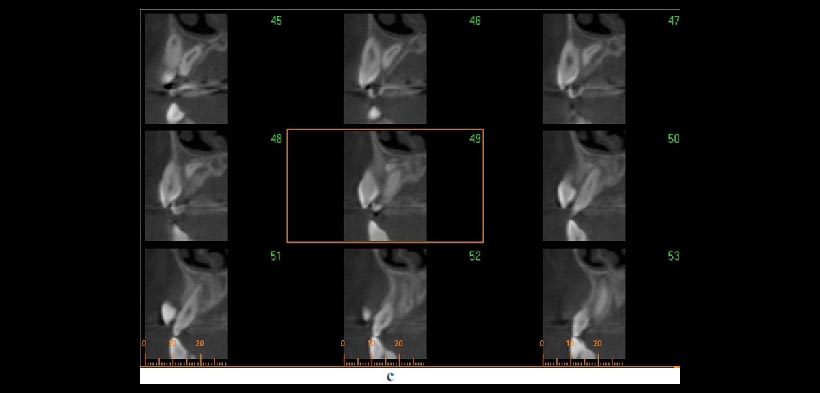

- DETERMINACIÓN ESPACIAL DE LA CORONA Y RAIZ (MORFOMETRÍA DENTOALVEOLAR): Ayuda en la determinación de las angulaciones de raíz, ofrece una evaluación precisa de la altura del hueso alveolar, sin embargo la CBCT da un número de falsos positivos en la determinación de las fenestraciones, por ende, se debe tener cuidado con respecto a la evaluación estos defectos en las imágenes (fig.2).

Figura 2. Uso de la CBCT en el diagnóstico y la planificación del tratamiento de los dientes transpuestos. Un caso que demuestra raíces transpuestas de los caninos superiores y los primeros premolares en la que la CBCT revela que la raíz canina está a vestibular de la raíz premolar. (a) Reconstrucción tridimensional y (b, c) imágenes transversales y la ubicación de la raíz. Todos estos cortes tomográficos pueden ayudar al clínico a optimizar la planificación del tratamiento.